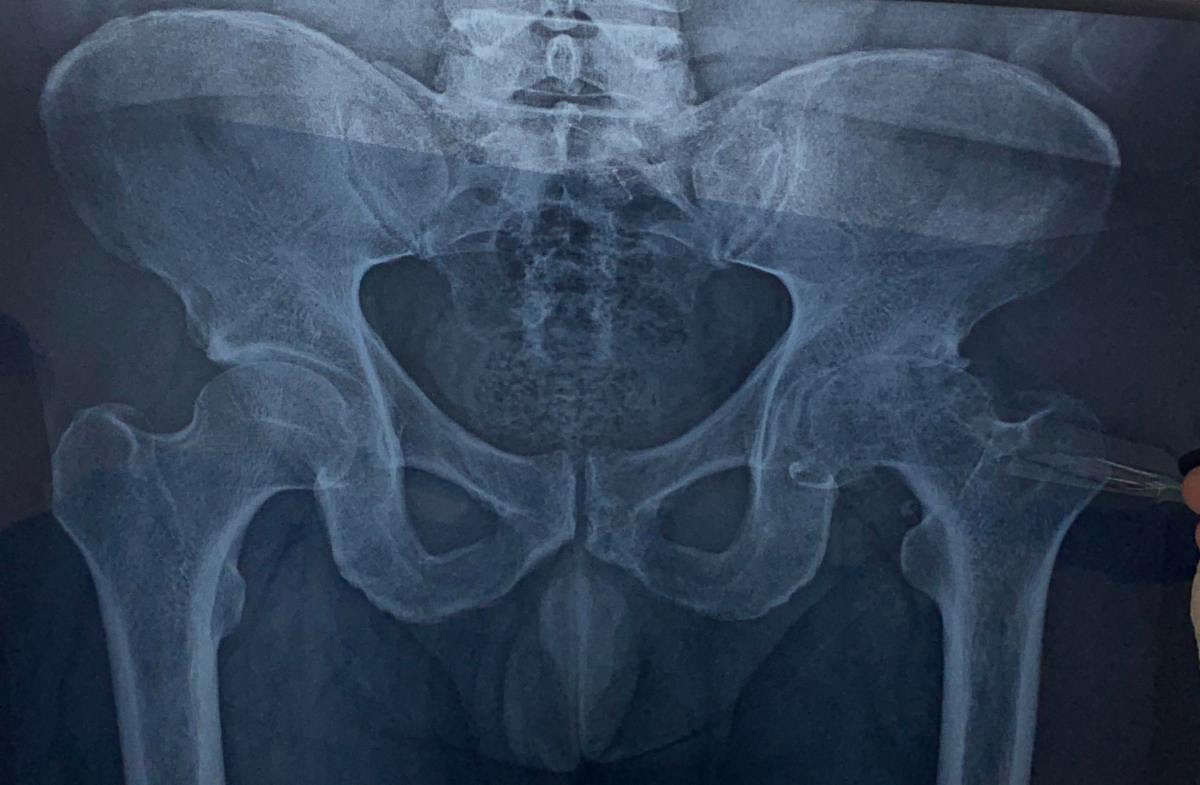

Hip replacement starts with an x-ray to show the state of the hip prior to surgery. Notice the deterioration on the right side.